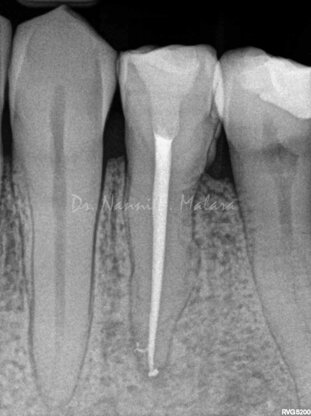

Premolare affetto da lesione periapicale (Alla radiografia si presenta come area scura intorno alla radice)

Terapia endodontica con sigillo tridimensionale del sistema canalare

Il controllo radiografico eseguito ad 8 mesi evidenzia l'avvenuta guarigione con il riassorbimento completo della lesione apicale.